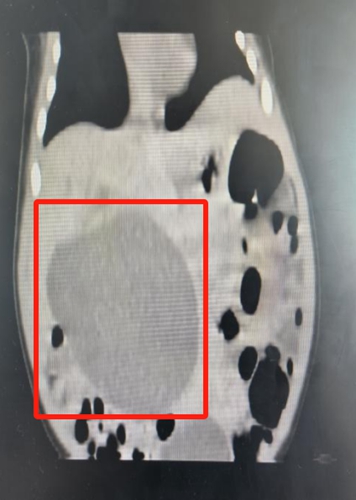

安安出生后,新生兒外科、NICU、新生兒內(nèi)科、產(chǎn)科等科室再次進行MDT會診,進行了全面評估,檢查結(jié)果顯示:膽總管囊腫,3*3cm。

△安安的囊腫迅速長到6*5cm,小小的身體里埋著一個雞蛋大小的“炸彈”。

救治團隊邊控制黃疸病情,穩(wěn)住肝功能,邊根據(jù)預案密切觀察,發(fā)現(xiàn)寶寶的囊腫在短時間內(nèi)迅速增大,7天內(nèi)從最初的3*3cm增長到6*5cm。